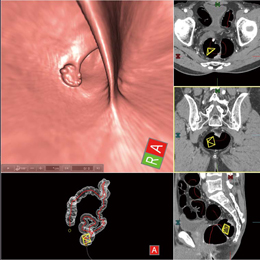

・仮想内視鏡像であるフライスルー画像(図1)

・フライスルー画像にMPR像をフュージョンさせたフライスルー+MPR像(図2)

図1 フライスルー画像 |

図2 フライスルー+MPR像 |

フライスルー画像では,設定された芯線に沿って移動しながら,大腸内腔の壁面形状の観察ができる。観察方向は,任意に変更できるため,襞の間の観察も容易に行うことができる。また,フライスルー+MPR像に切り替えることで,腸管内だけでなく,大腸周辺の組織や病変などの断面構造を併せて観察することができる。さらに,フィレビュー画像においては,大腸内壁の状態を一望することが可能である。